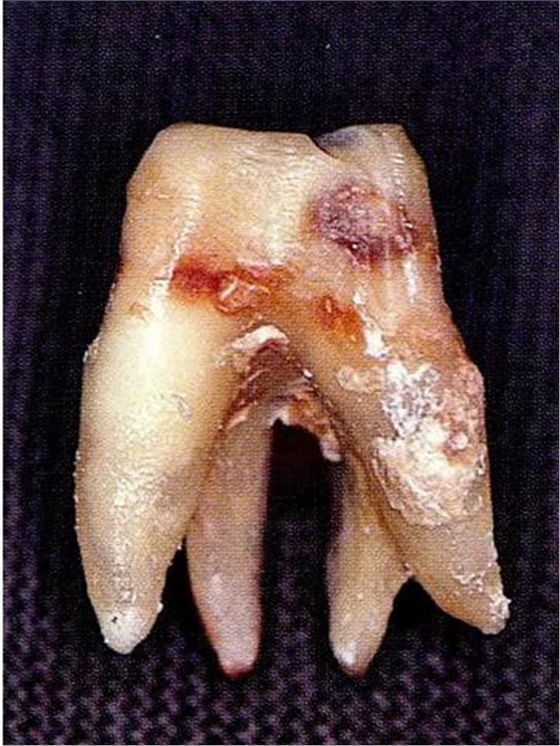

▼圖6-3上頜第一后磨牙的牙根形態(tài)異常。舌側(cè)面觀察。

[融合牙]

▼圖6-4下頜第二后磨牙的融合根。在根尖的組合部的產(chǎn)生了附著喪失,導(dǎo)致急速惡化。